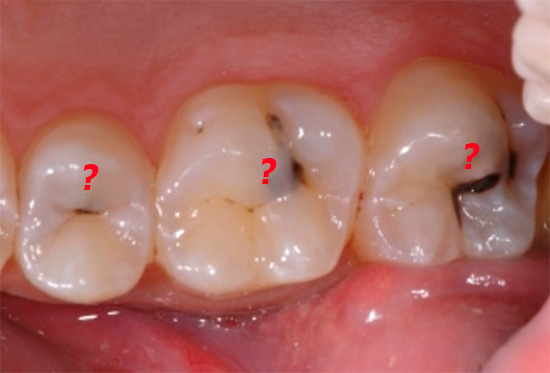

Ma come distinguere i segni della pulpite da altre malattie del dente (diciamo, dal forte dolore con carie profonde), quali complicazioni possono minacciare e se esistono modi per prevenirle - questo e molto altro verranno discussi in seguito.

Quasi il 70-80% delle informazioni sulla forma di pulpite del dente può essere ottenuto sulla base di una valutazione dei sintomi e di uno studio della cavità cariata quando esaminato da uno specchio dentale e durante il sondaggio. Uno studio oggettivo ci consente di distinguere la pulpite da carie profonde, varie forme di parodontite, ecc.

Il sondaggio consente di capire se la camera pulpare del dente è aperta, se è doloroso sondare, se il “nervo” aperto sanguina, se il dente stesso è scolorito, se c'è dolore durante la percussione (toccando il dente con l'estremità smussata della maniglia della sonda) - tutto questo ha anche importanza per la diagnosi accurata e il successivo trattamento.